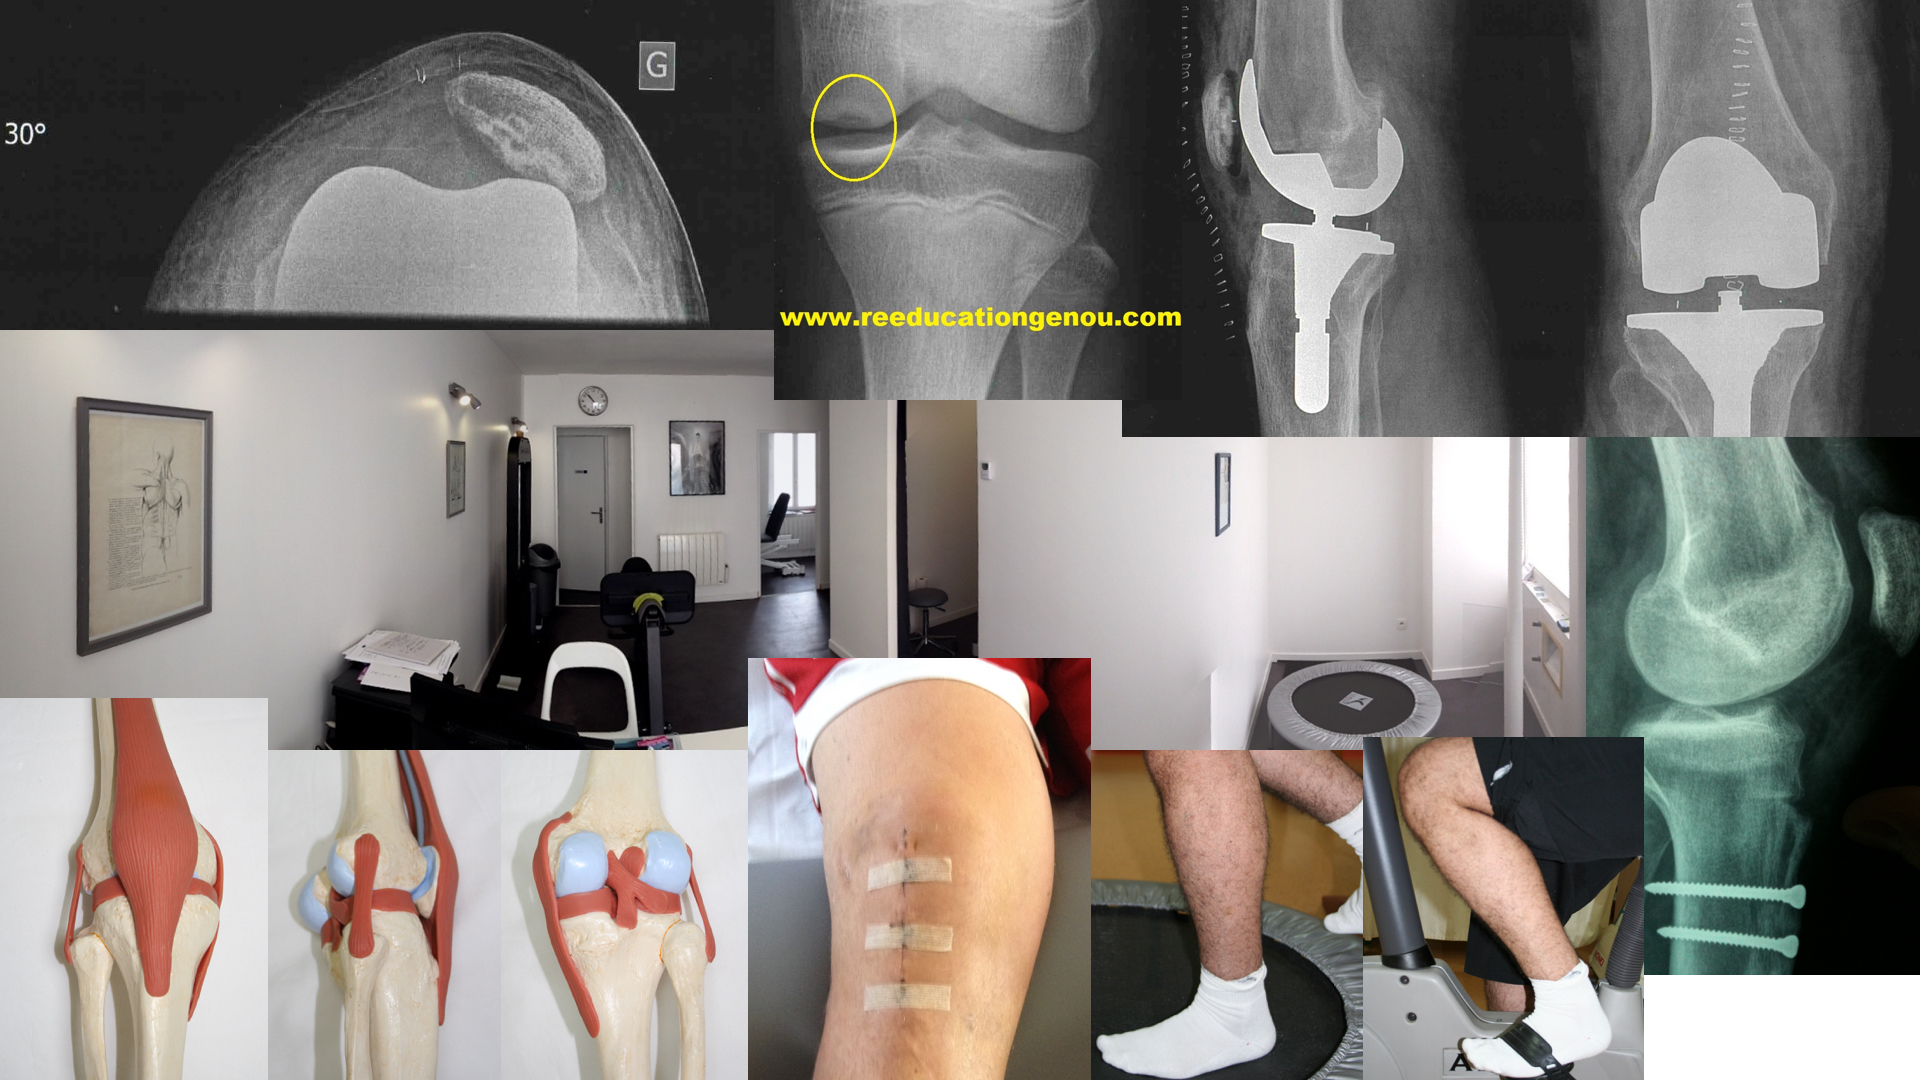

• Le cyclope syndrome est rare, il limite l'extension du genou parfois jusqu'à 20° de flexum par hyper-cicatrisation= kyste autour du pied de la plastie du LCA. La fin d'amplitude d'extension est ressentie par le kiné comme dure et inextensible. La solution, dont la décision revient au chirurgien seul peut être une arthroscopie pour nettoyer tout ça, enlever le kyste ce qui libère de suite l'extension et la flexion complète.

• Soit ce déficit est prévu par l'ajout d'une suture méniscale ou une réparation ligamentaire / musculaire soit la sensation en fin d'extension est dure et douloureuse...Ce dernier cas qui frole les 1,5% des genoux n'obtenant pas l'extension à 2 mois post-opératoire peut être la conséquence d'un CYCLOP SYNDROME.

• en cas de doutes il faut tester la qualité de la fin de l'extension. si c'est un point dur que l'on retrouve ajouté à un flexum cela peut effectivement être un cyclope. Donc avis chirurgical